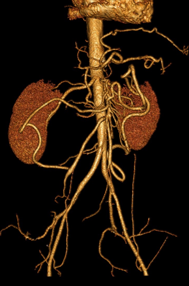

L’essentiel sur l’ischémie intestinale aiguë en imagerie

DANSE E. - UCL

Année académique 2020-2021

Digestif DES BASE